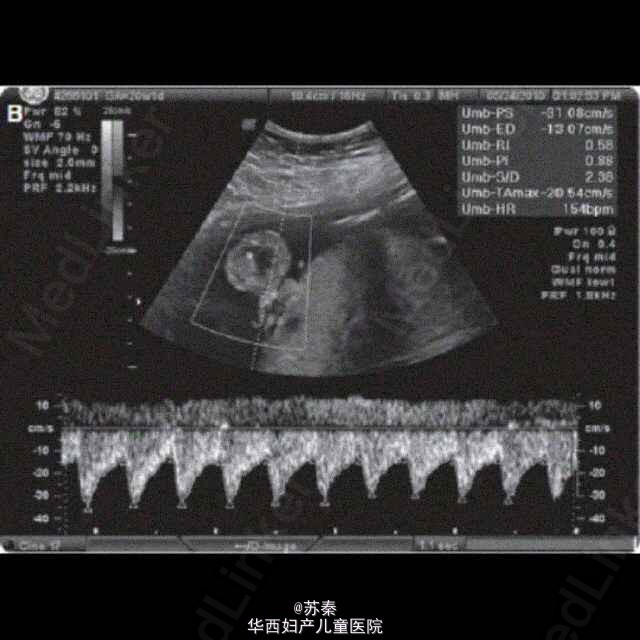

37岁女性,G4P1031,孕20周做超声提示在胎儿口腔内有一带蒂囊性含固体内容物的肿块。多普勒显示该肿瘤的动静脉图像。MRI提示在胎儿脸部靠近正中偏左处发现外生型复杂肿块,未发现颅内转移。 各种影像学资料综合,提示为胎儿的口腔部畸胎瘤。 选择做胎儿镜经胎儿嘴唇和上颚将肿块去除。 产妇生产后,检查胎儿口腔,无明显裂痕,伤口或残余肿块。